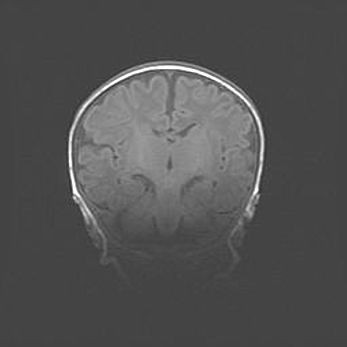

Наружная гидроцефалия с возможной атрофией височных областей.

Возраст: 28 дней

Вес: 3670 г

Пол: мужской

Окружность головы: 38 см

Срок гестации: 40 недель

Гидроцефалия головного мозга у новорожденных – это заболевание, которое характеризуется скоплением избыточного количества спинномозговой жидкости в желудочковой системе головного мозга в результате затруднения её перемещения от места выработки к месту поглощения в кровеносную систему или вследствие нарушения абсорбции. При открытой наружной форме гидроцефалии у новорожденных расширяются и переполняются субарахноидные пространства.

При нормотензивных  формах,  которые,  как  правило,  являются  следствием  перенесенных ишемических  повреждений  паренхимы  мозга,  возможно  сочетание микроцефалии  с нормотензивной гидроцефалией. В основе данных изменений лежит атрофия больших полушарий с преимущественной  локализацией  в  лобно-височных  областях.